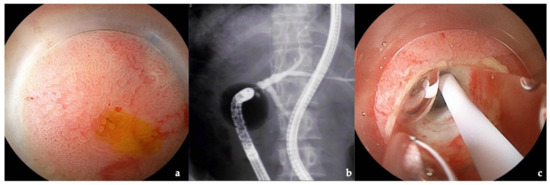

3.4. Intussusception Antireflux Valve